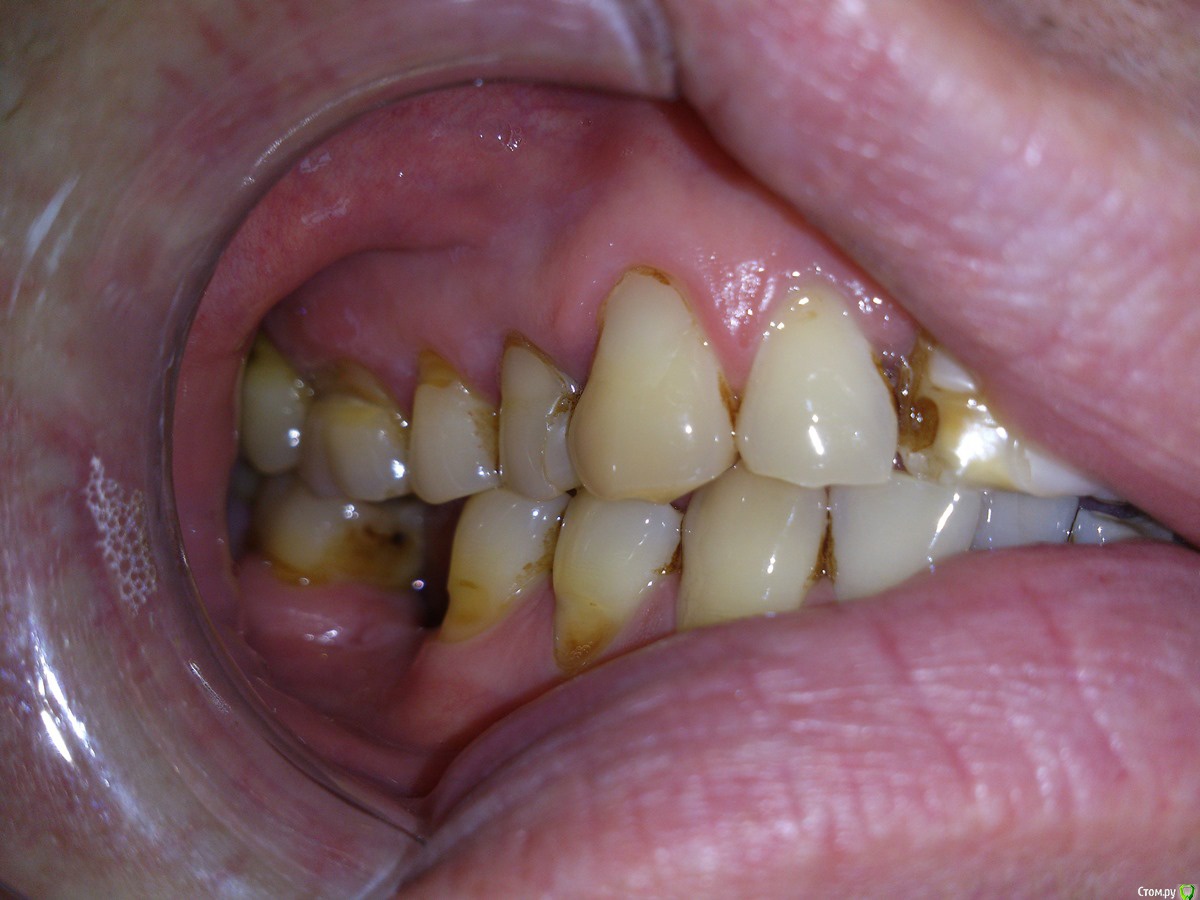

SanderS Опубликовано 6 февраля, 2016 Поделиться Опубликовано 6 февраля, 2016 Пациенту не нравится фронт и пришеечные дефекты, перелечены несколько зубов. Из анамнеза - привычка "стискивать зубы", или как говорит - "попадаю на какой то зуб и начинаю двигать челюсть влево вправо не задумываясь", появилось лет 10 назад, сейчас 35.Возможно обойтись без тотала с каппой, или не браться вообще? Ссылка на комментарий

Ronin Опубликовано 7 февраля, 2016 Поделиться Опубликовано 7 февраля, 2016 Решение оптимальное, как сказал коллега выше, восстановить фронт и клыковое ведение, но как ограничиться этим, ведь бока тоже нужно делать.. там же эндо, как я понял и так делается, одного моляра нет?! реставрации композиционные что ли? Надо учитывать "стискивание" , разломает потом эти зубы и все, плюс расхождение зубов тоже есть, перегрузка, не забудем и про пародонтальный комплекс, высоту поднять, если нужно, предварительно определив, хотя высота, как мне кажется в порядке, но могу ошибаться, на завершающем этапе обязательно каппу, ношение максимальное время! Здесь важно хуже не сделать, если нет уверенности в стабильном результате, ибо не навреди... Если уверенны, то только в путь))) Ссылка на комментарий

SanderS Опубликовано 8 февраля, 2016 Автор Поделиться Опубликовано 8 февраля, 2016 те что после перелечивания естественно будут покрываться коронками, нижний моляр имплантат, если пришеечные дефекты реставрировать композитом при условии восстановления клыковой направляющей + каппа, не повыпадают ли они? Высота у него вроде не снижена, за счет компенсации. Ссылка на комментарий

Ronin Опубликовано 8 февраля, 2016 Поделиться Опубликовано 8 февраля, 2016 те что после перелечивания естественно будут покрываться коронками, нижний моляр имплантат, если пришеечные дефекты реставрировать композитом при условии восстановления клыковой направляющей + каппа, не повыпадают ли они? Высота у него вроде не снижена, за счет компенсации.Пломбы не простоят долго, здесь даже подсказка, что клиновидные дефекты, повсеместно, что перегрузка, упругие деформации в действии имеют место быть. Как временное мероприятие, если средств нет пока заниматься, но лучше уточнить высоту и оставить все на временных до возможности финансово заняться, или билдап сделать на боковых из композита самостоятельно или по вакс-апу, лучше второе. Ссылка на комментарий